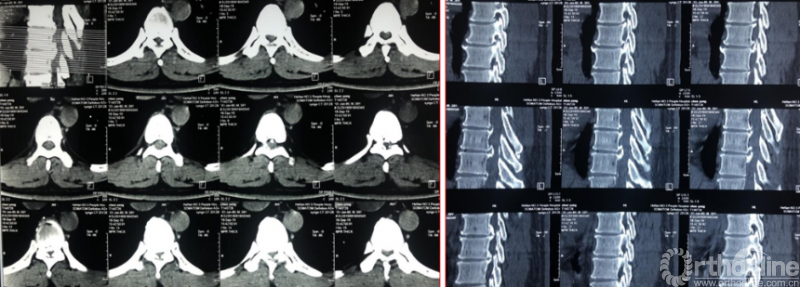

Case4:胸椎间盘突出伴韧带钙化可视化治疗

术前诊断及评分

JOA评分:5分

ASIA等级:C级

诊断:

1:胸椎间盘突出伴钙化下肢不全瘫

术前资料

术后影像学资料

术后病情评估

术后第二天

JOA评分:8分;RR:37.5%(可);ASIA等级:D级。

术后8个月资料